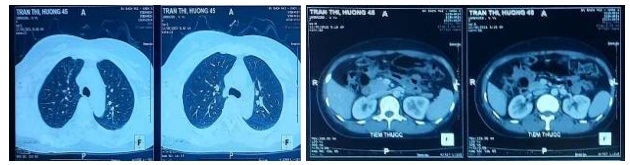

- Chụp cắt lớp vi tính ngực bụng: chưa phát hiện tổn thương di căn xa.

Hình 4. Cắt lớp vi tính ngực, bụng, tiểu khung có tiêm thuốc.